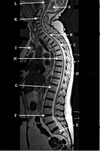

What is letter A?

4TH VENTRICLE

What is letter B?

CEREBELLUM

What is letter C?

POSTERIOR ARCH OF C1

What is letter D?

A

What is letter E?

CSF

How well did you know this?

1

Not at all

2

3

4

5